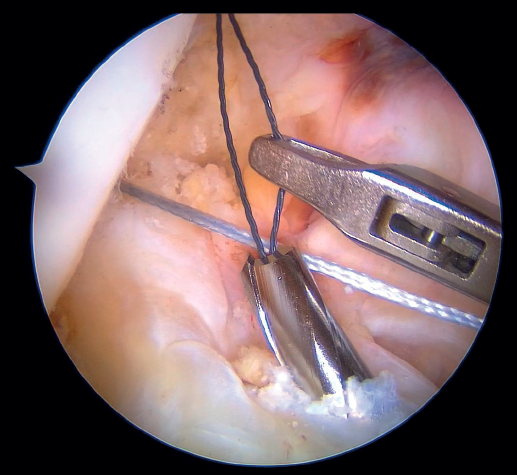

Outside the knee, the threads are loaded into a knotless anchor implant with a tape that will act as anterior reinforcement of the ACL when attached to the tibia. Once the implant has been loaded, it is inserted into the previously prepared site. This step is facilitated when viewing is made from the anteromedial portal, as it affords a better perspective of the zone (Figure 5). Once the implant has been inserted, the suture threads are cut at the level of the condylar wall.

With vision through the anterolateral portal, the tibial guide of the ACL is placed in the central zone of its distal insertion, and a tunnel is made with a 2.4 mm cannulated drill through which a loop-ended nitinol is passed and retrieved through the accessory anteromedial portal. The nitinol serves as a retriever, to load the tape through it and pass it through the tibial tunnel. Once the tape is retrieved, it is secured to the tibial cortex with a knotless anchor implant or button, tightening the tape with the knee in near full extension. If a threaded implant is used, it is important to check that no implant threads protrude at the cortex, as this could cause discomfort in the future.

Under arthroscopic vision, it is important to confirm tension of the ACL both in the full range of motion and with the use of a palpator and the Lachman and anterior drawer maneuvers (Figure 6).